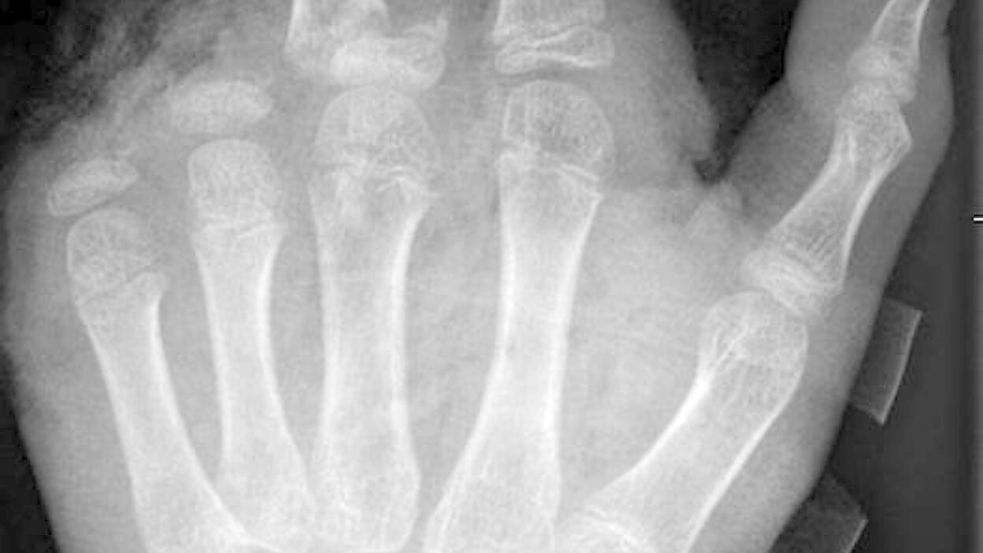

So kann ein Röntgenbild nach einer missglückten Böllerexplosion aussehen: Zwei Finger fehlen. Foto: -/UKB/dpa